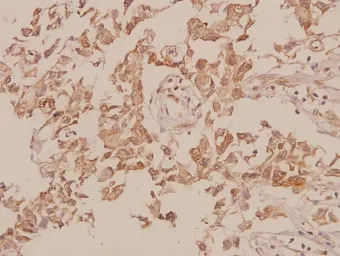

Immunohistochemistry (IHC) analyzes of M-cadherin (GTX17434) pAb in paraffin-embedded human breast carcinoma tissue at 1:50.